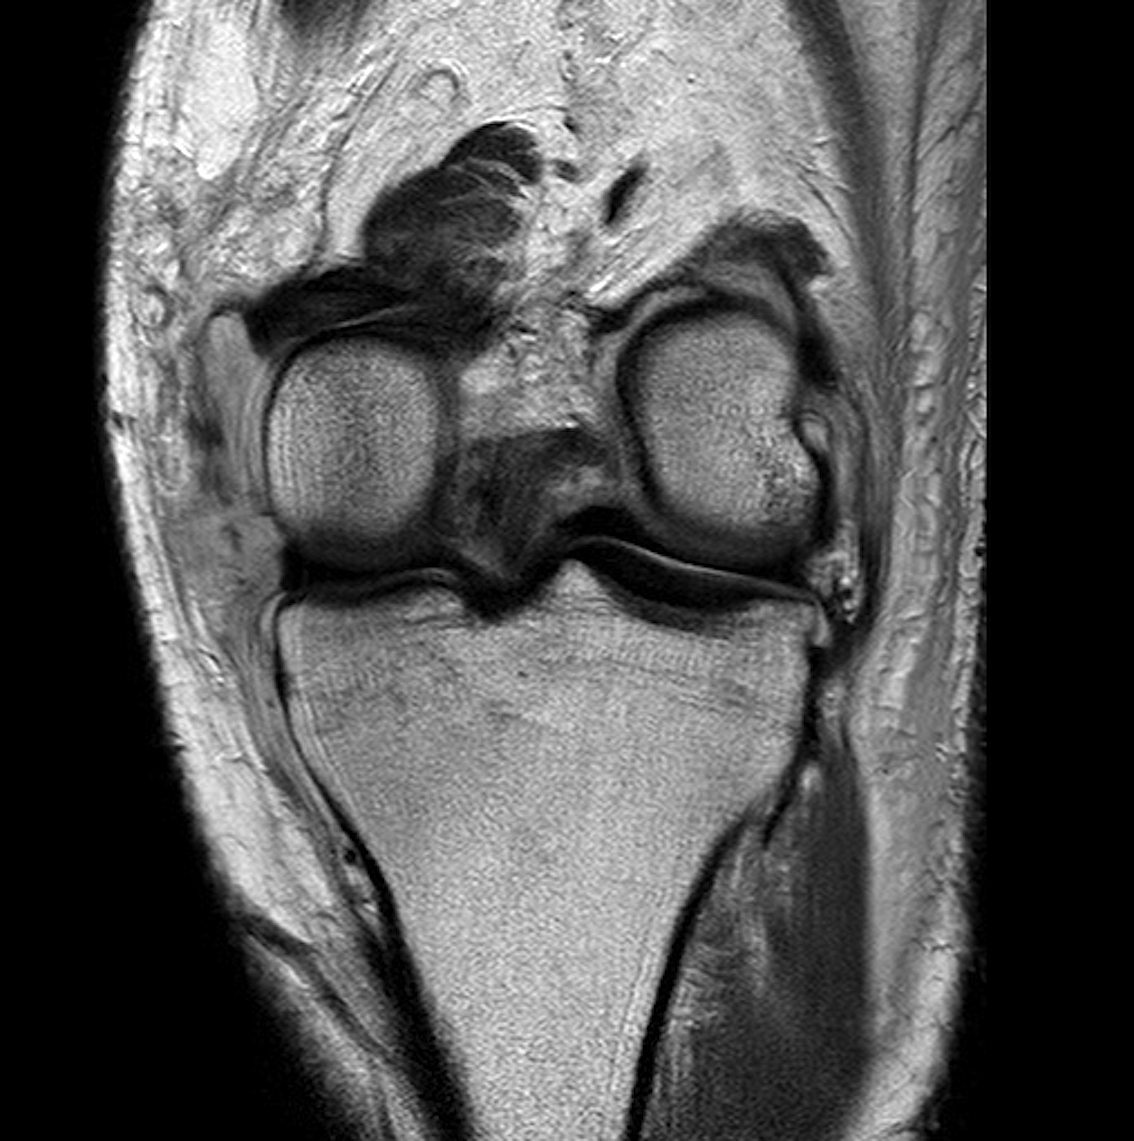

After an MRI to diagnose the degree of damage, and careful clinical examination, it is often best initially to rehabilitate the knee to restore range of motion and reduce swelling. Medial collateral ligament (MCL) injuries can often heal on their own, with rehabilitation, bracing, and non weight bearing.